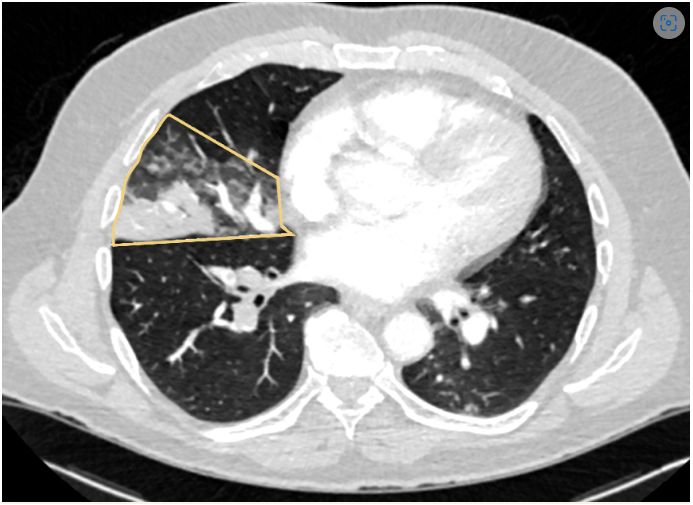

Pulmonary infarction - large wedge shaped